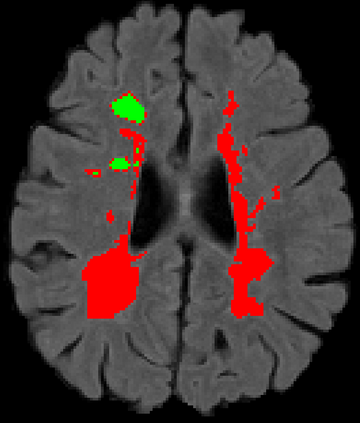

Recently, segmentation methods based on Convolutional Neural Networks (CNNs) showed promising performance in automatic Multiple Sclerosis (MS) lesions segmentation. These techniques have even outperformed human experts in controlled evaluation conditions such as Longitudinal MS Lesion Segmentation Challenge (ISBI Challenge). However state-of-the-art approaches trained to perform well on highly-controlled datasets fail to generalize on clinical data from unseen datasets. Instead of proposing another improvement of the segmentation accuracy, we propose a novel method robust to domain shift and performing well on unseen datasets, called DeepLesionBrain (DLB). This generalization property results from three main contributions. First, DLB is based on a large group of compact 3D CNNs. This spatially distributed strategy ensures a robust prediction despite the risk of generalization failure of some individual networks. Second, DLB includes a new image quality data augmentation to reduce dependency to training data specificity (e.g., acquisition protocol). Finally, to learn a more generalizable representation of MS lesions, we propose a hierarchical specialization learning (HSL). HSL is performed by pre-training a generic network over the whole brain, before using its weights as initialization to locally specialized networks. By this end, DLB learns both generic features extracted at global image level and specific features extracted at local image level. DLB generalization was validated in cross-dataset experiments on MSSEG'16, ISBI challenge, and in-house datasets. During experiments, DLB showed higher segmentation accuracy, better segmentation consistency and greater generalization performance compared to state-of-the-art methods. Therefore, DLB offers a robust framework well-suited for clinical practice.